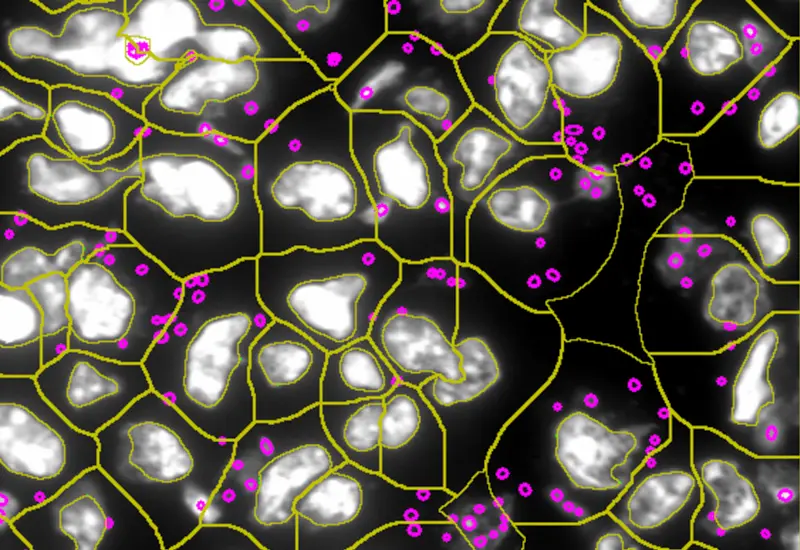

The IF Cellular Contact App allows for the determination of the cellular phenotype of specific IF-stained cell populations and establishes the cellular contacts to their neighboring cells (the number of markers is technically unlimited). If needed, the App provides a separation of nuclei in tissues with high cellular densities. The App outputs parameters such as staining intensity per marker and morphometric parameters for each segmented cell/cell compartment, as well as the number and percentage of cells of different phenotypes in direct contact.

Images: courtesy of Naoki Kaneko/Shiv Pillai (PI), Ragon Institute of MGH, MIT and Harvard, Boston, MA USA.